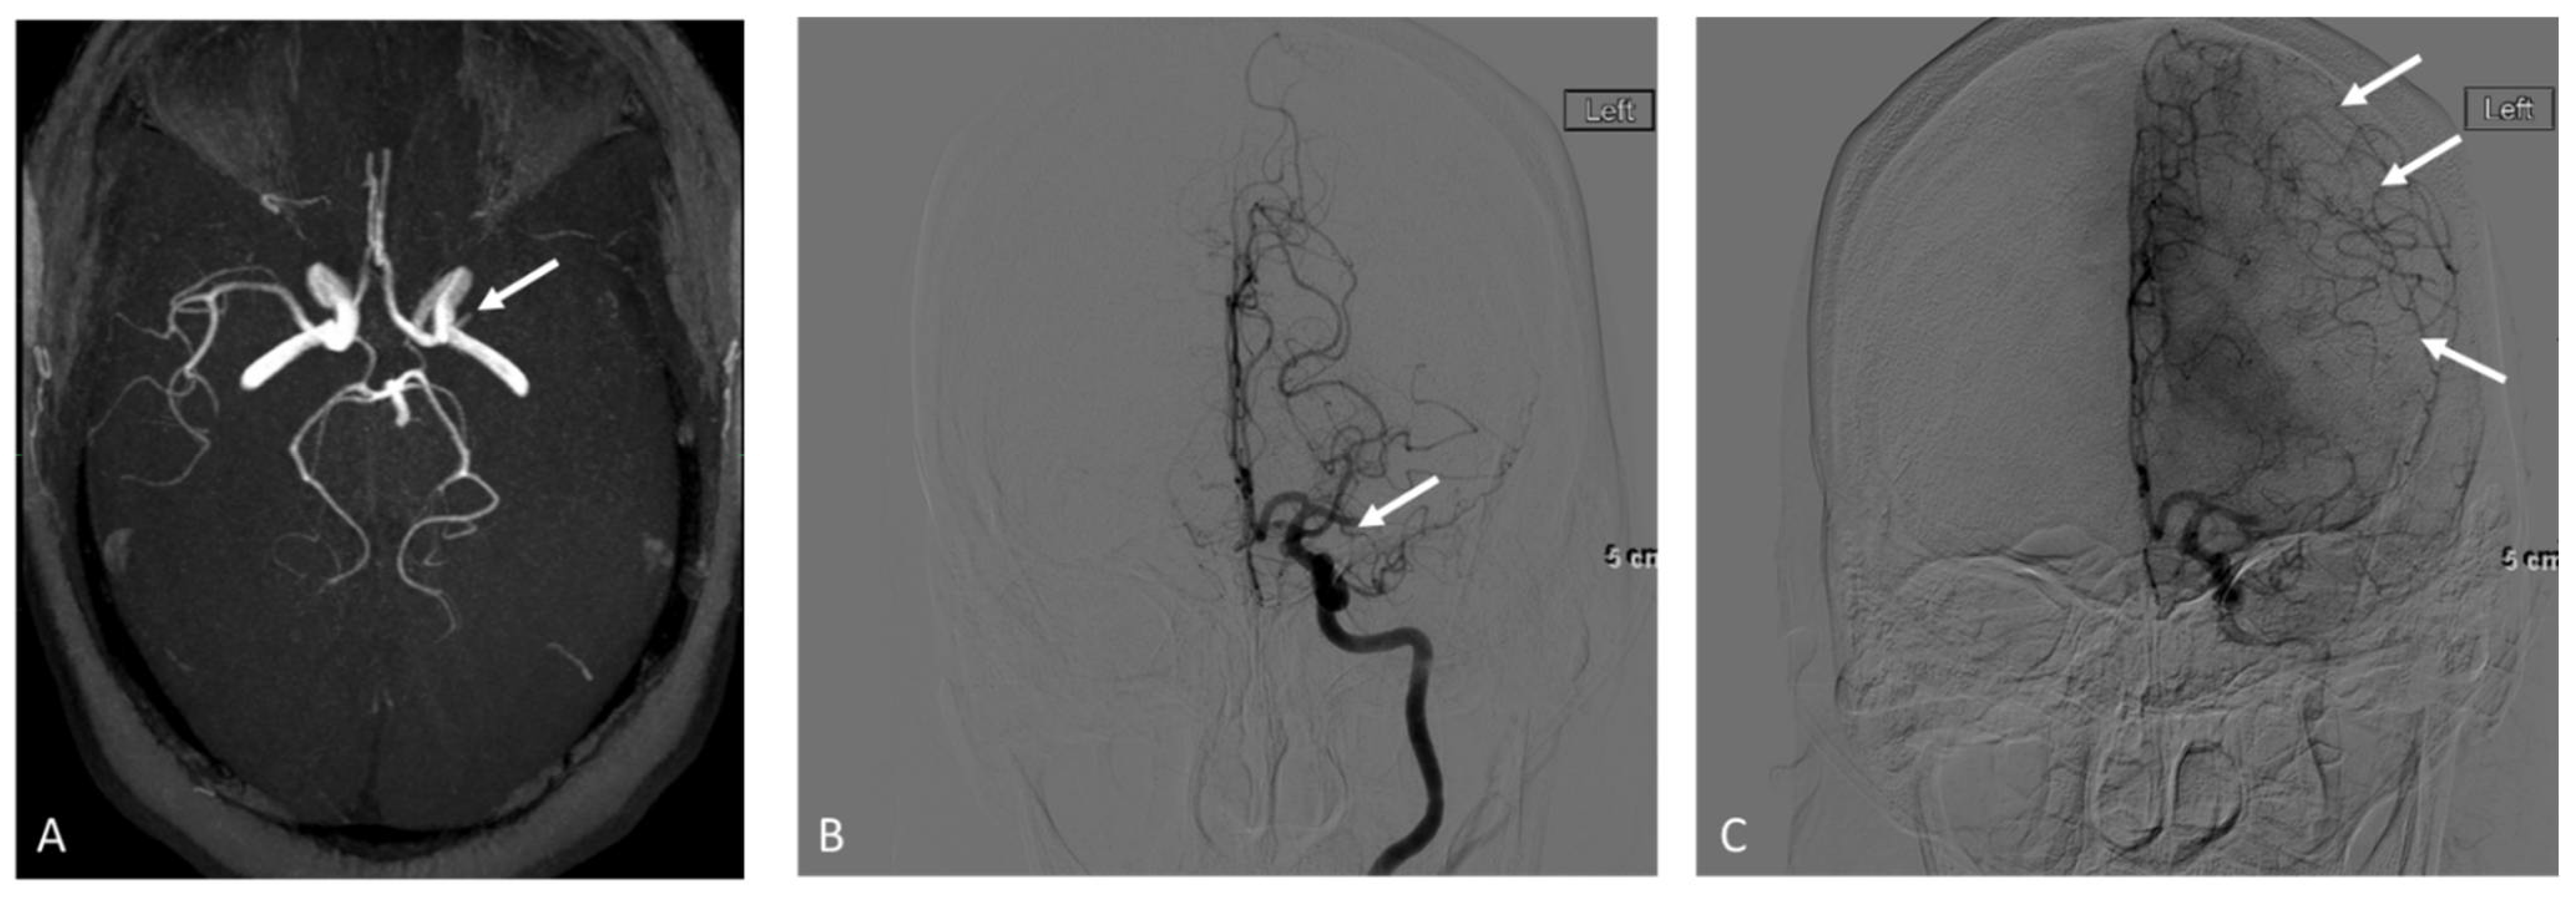

2.3.1. MRA

2.3.2. DSA